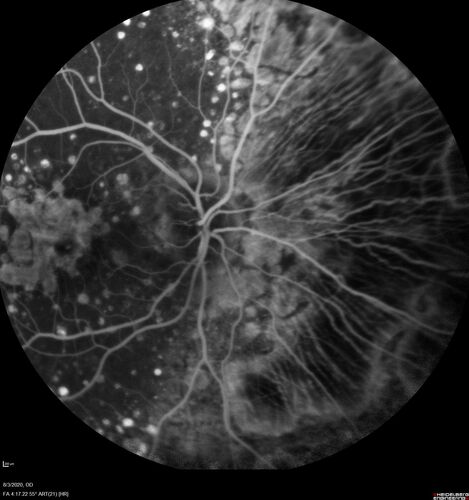

Dry AMD geographic atrophy and cystoid macular edema

79 year old vision is in for a checkup with no visual complaints in the left eye.  This is her better eye.  VA 20/200 OD, 20/50 OS.  3 years ago she had a CRVO in the left eye.  She is also diabetic for 20 years, has carotid insufficiency and anemia.  Left eye shows CME.  This was not treated and the vision improved to 20/40 over the next year although mild edema persisted.